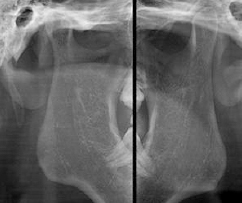

3D CT 촬영으로 치아와 치조골의 상태 및

잇몸뼈의 양과 길이 등의 상태를 정확하게

측정하여 세밀한 진단과 시술 전 발생가능한

문제점을 사전에 발견하고 대비하여

진료의 안정성을 높힙니다.

치과진료는 굉장히 세밀한 치료이기 때문에 정밀한 3D 디지털 기술을 접목하면

의료진의 판단에만 의존하던 치료를 더욱 정확하게 예측하고 진하여 오차를 줄일 수 있습니다.